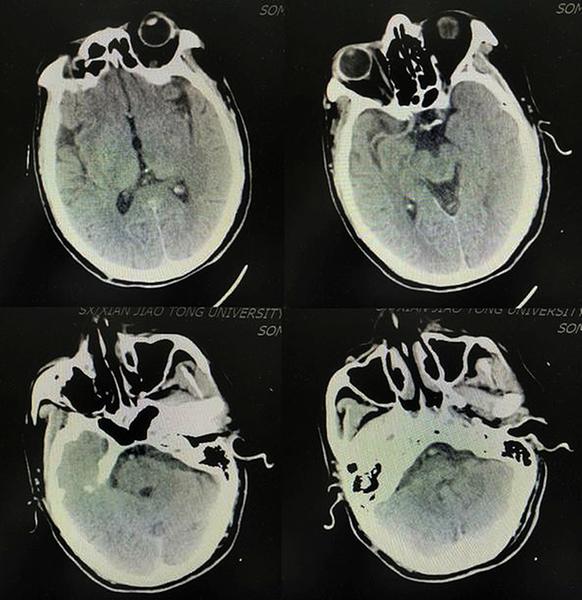

术后复查颅脑CT无脑出血转化

患者术前及术后的脑血管造影DSA对比图